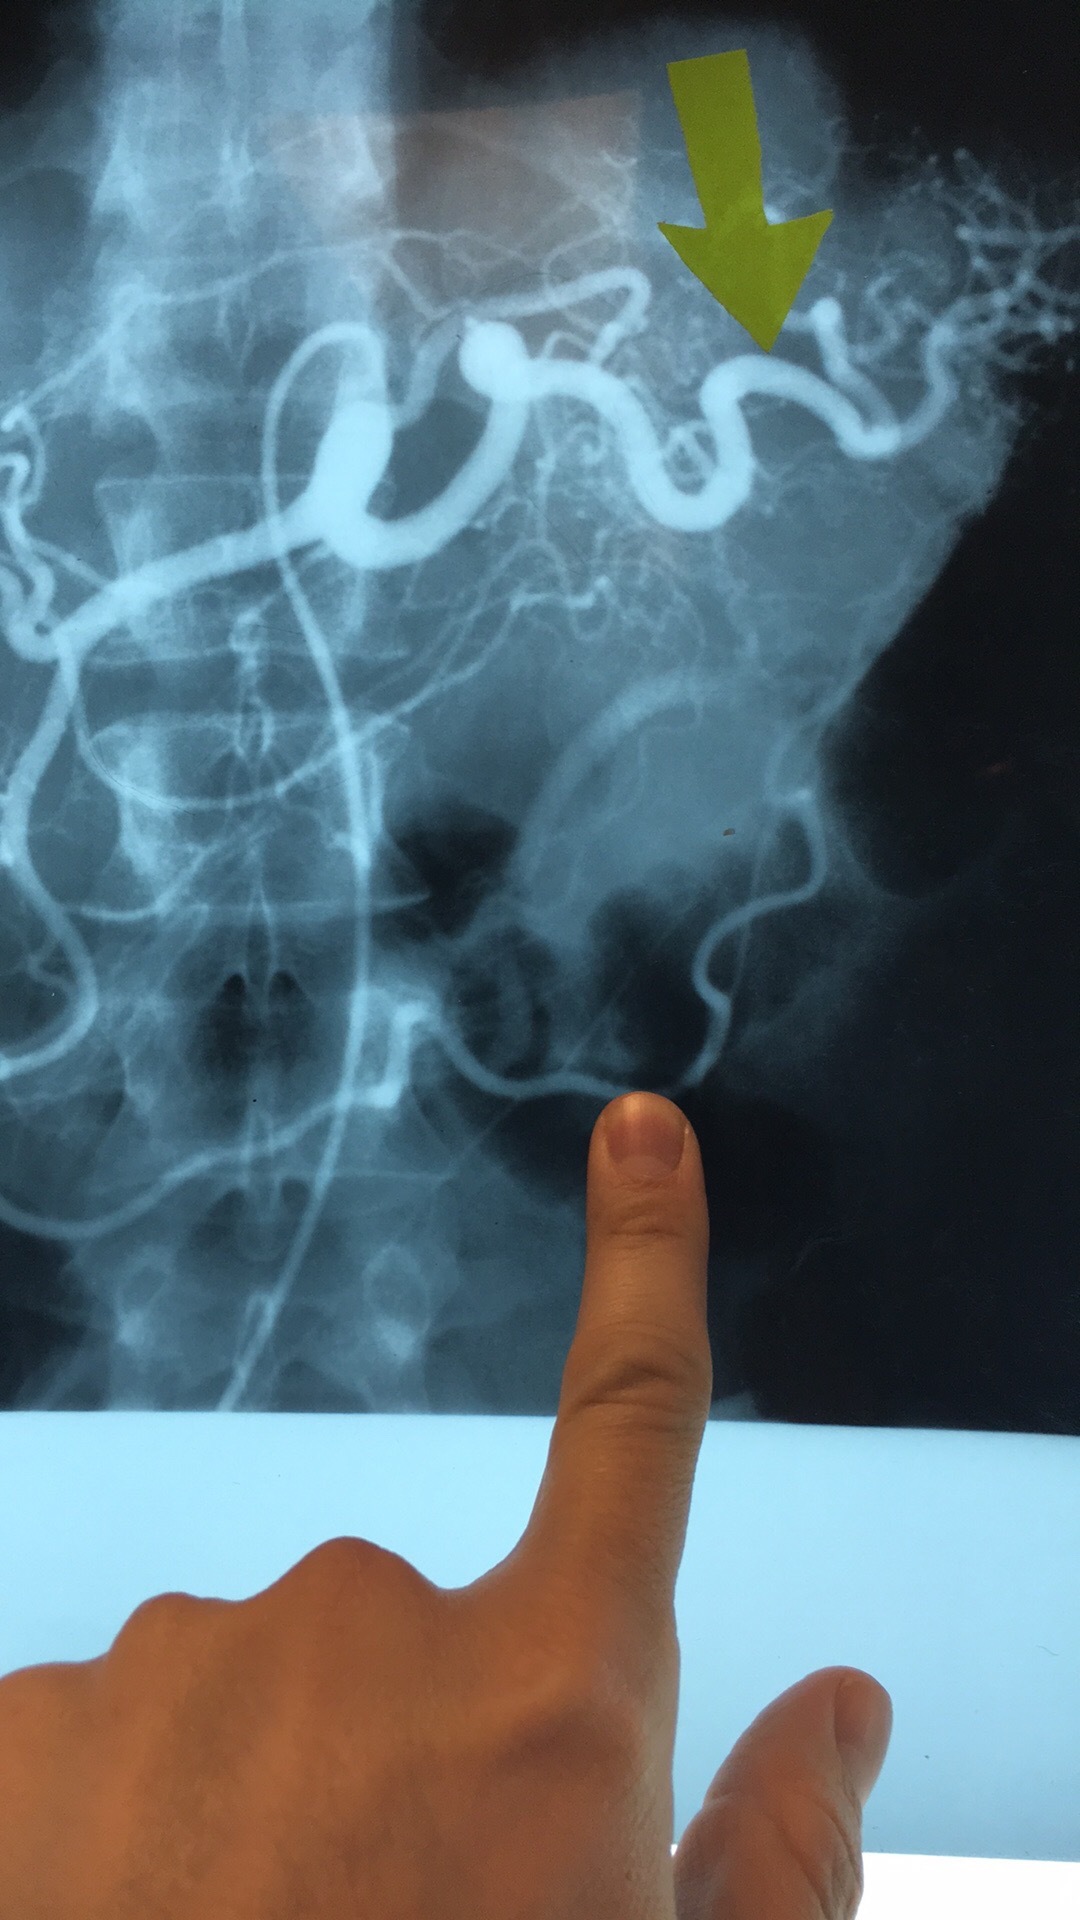

Which artery? What are the branches?

Celiac Trunk. Left Gastric Art, Common Hepatic Prtery, and Splenic Art